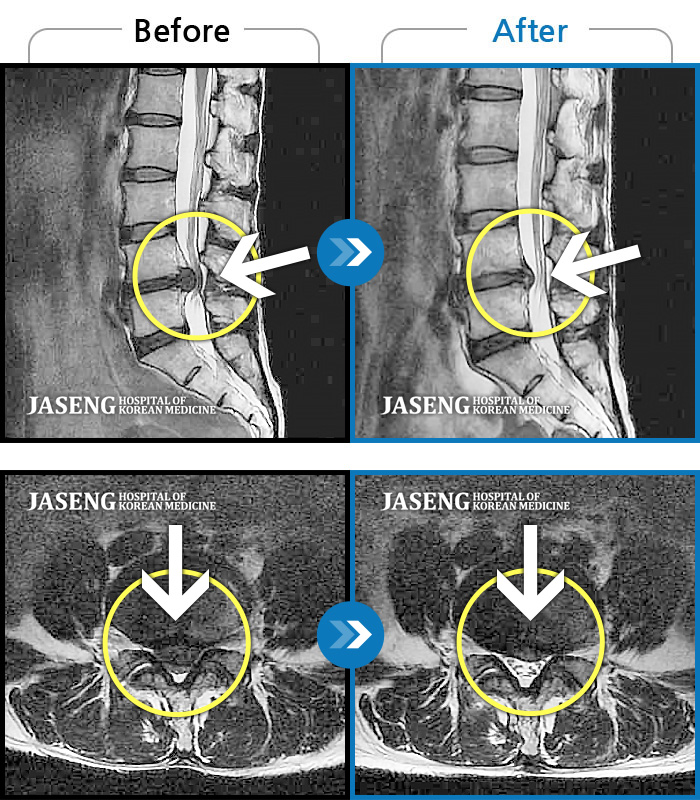

허리디스크

많이 본 사례

수원 · 김태성 원장

허리 통증과 좌측 대퇴부 저림과 당김

촬영시기

2023.02.03 ~ 2024.02.14

2024.11.21